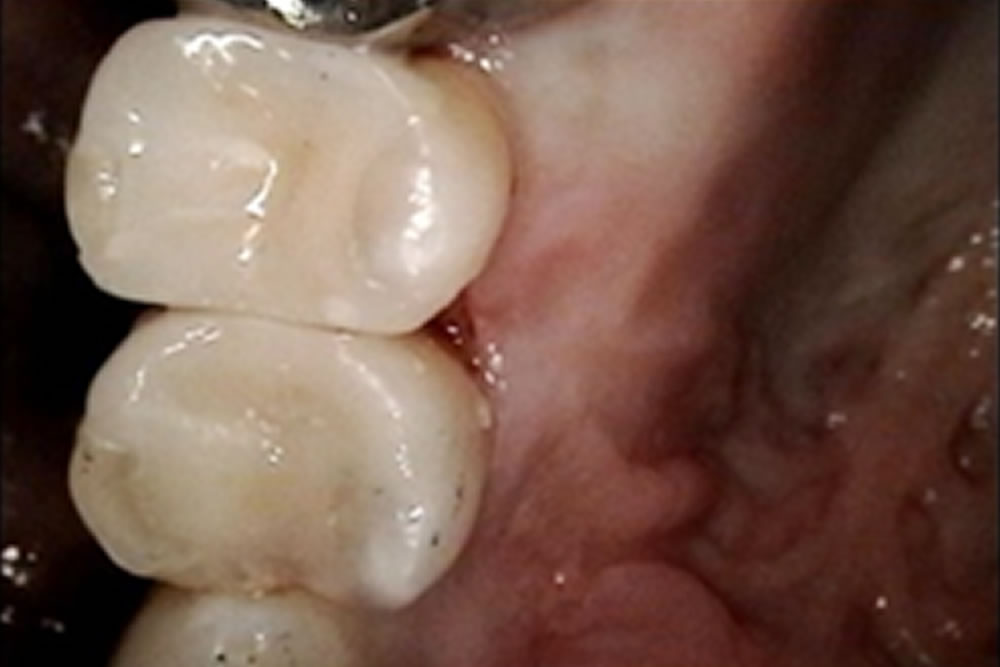

セラミックインレーの装着・治療完了

3週間後、セラミックインレーが出来上がってきたので接着を行いました。